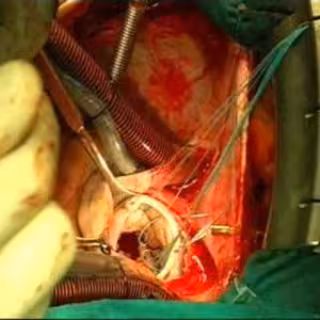

Añadió que tras la prueba endoscópica, que se realizó el pasado 30 de agosto y que duró apenas 10 minutos, la paciente permaneció 24 horas en Observación y monitorizada en la Unidad Coronaria, al objeto de controlar el comportamiento del corazón. Posteriormente, en concreto el 28 de septiembre, la paciente fue operada "mediante una cirugía rutinaria que no duró más de 45 minutos", prosiguió Infante.